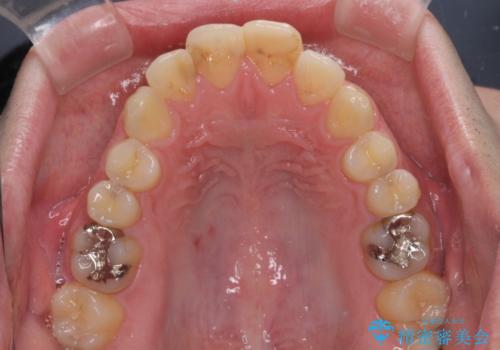

- 口がうまく閉じられないとのことで来院された患者様です。

上下唇をしっかり合わせようとすると、顎先が前方に突出してしまうほど口が閉じにくい状態でした。

口元の突出感を改善するために上下左右の第一小臼歯4本を抜歯し、ワイヤー装置にて矯正治療を行うこととしました。

また、上下前歯は舌の突出癖による開咬となっていたため、舌のトレーニングを徹底するよう指示しました。